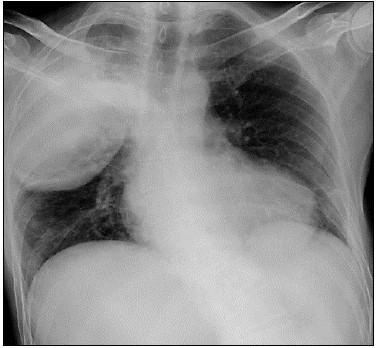

Homem, 56 anos, deu entrada na emergência com quadro de tosse, hemoptise, febre e fraqueza muscular há uma semana. Exame físico: regular estado geral; desidratado; taquipneico; FR = 28 irp. Auscuta pulmonar: estertores creptantes em hemitórax direito. Gram de escarro: presença de bastonetes gram-negativos. Analise a radiografia de tórax a seguir:

Qual o mais provável agente etiológico implicada neste caso clínico hipotético?